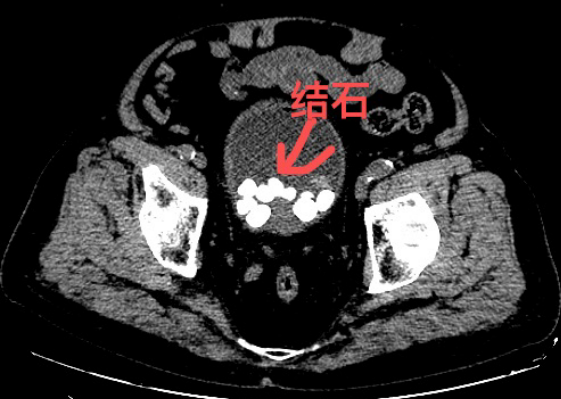

结石位置。通讯员供图

经详细检查,确诊为前列腺增生、膀胱多发结石。长期的前列腺增生导致尿路梗阻,尿液排出不畅,进而诱发膀胱结石,双重病症叠加,不仅严重影响排尿功能,血尿症状更提示病情危急,若不及时治疗,可能引发感染、肾功能损伤等严重并发症。考虑到患者年事已高,对手术耐受度有限,泌尿外科团队高度重视,立即组织麻醉科会诊,全面评估老人各项身体指标,反复研讨手术方案,最终决定采用膀胱碎石钳碎石取石术。该术式无需开刀,经尿道进入膀胱,精准击碎结石并完整取出,具有创伤小、出血少、恢复快等优势。